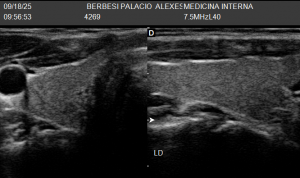

La ecografía tiroidea se realiza observando primero el istmo y luego cada lóbulo (derecho e izquierdo) en planos transversales y longitudinales. Así determinamos el tamaño y la presencia de nódulos, bocios o inflamación. Luego, si es necesario, usamos Doppler para ver el flujo y descartar actividad anormal.

LÓBULO TIROIDEO IZQUIERDO-ECOGRAFIA DE TIROIDES![]() | LÓBULO TIROIDEO DERECHO-ECOGRAFIA DE TIROIDES![]() |